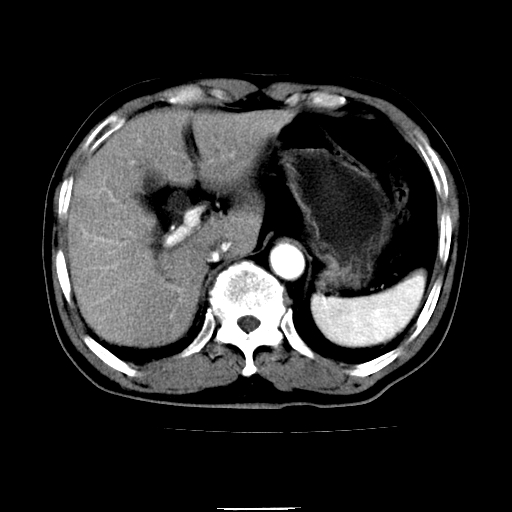

以下是引用chenqiong在2010-3-25 20:56:00的发言:[br]1、胆囊炎,胆囊息肉[br]2、肝内胆管及胆总管扩张,胆总管下端结石[br]3、十二指肠乳头旁憩室

以下是引用zxl51642在2010-3-26 10:47:00的发言:[br]胆囊炎,胆囊息肉,胆总管扩张,但未看到明显肿块,肝内胆管扩张不像恶性,炎性狭窄或阴性结石可能吧,建议mrcp,右肾小囊肿